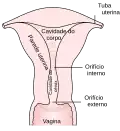

De fora para dentro, as camadas até o útero são:

- Vagina;

- Cérvix uterino - "colo do útero";

- Orifício externo do útero;

- Canal do cérvix;

- Orifício interno do útero;

- corpus uteri - "Corpo do útero";

- Cavidade do corpo do útero;

- Fundo (útero).

Anatomia do útero

Anatomia do útero -